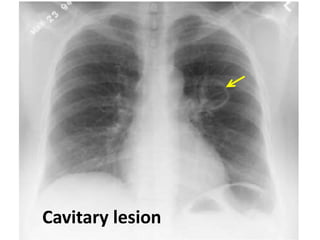

Cavitary tumour with air-fluid level

Cavitary lesion